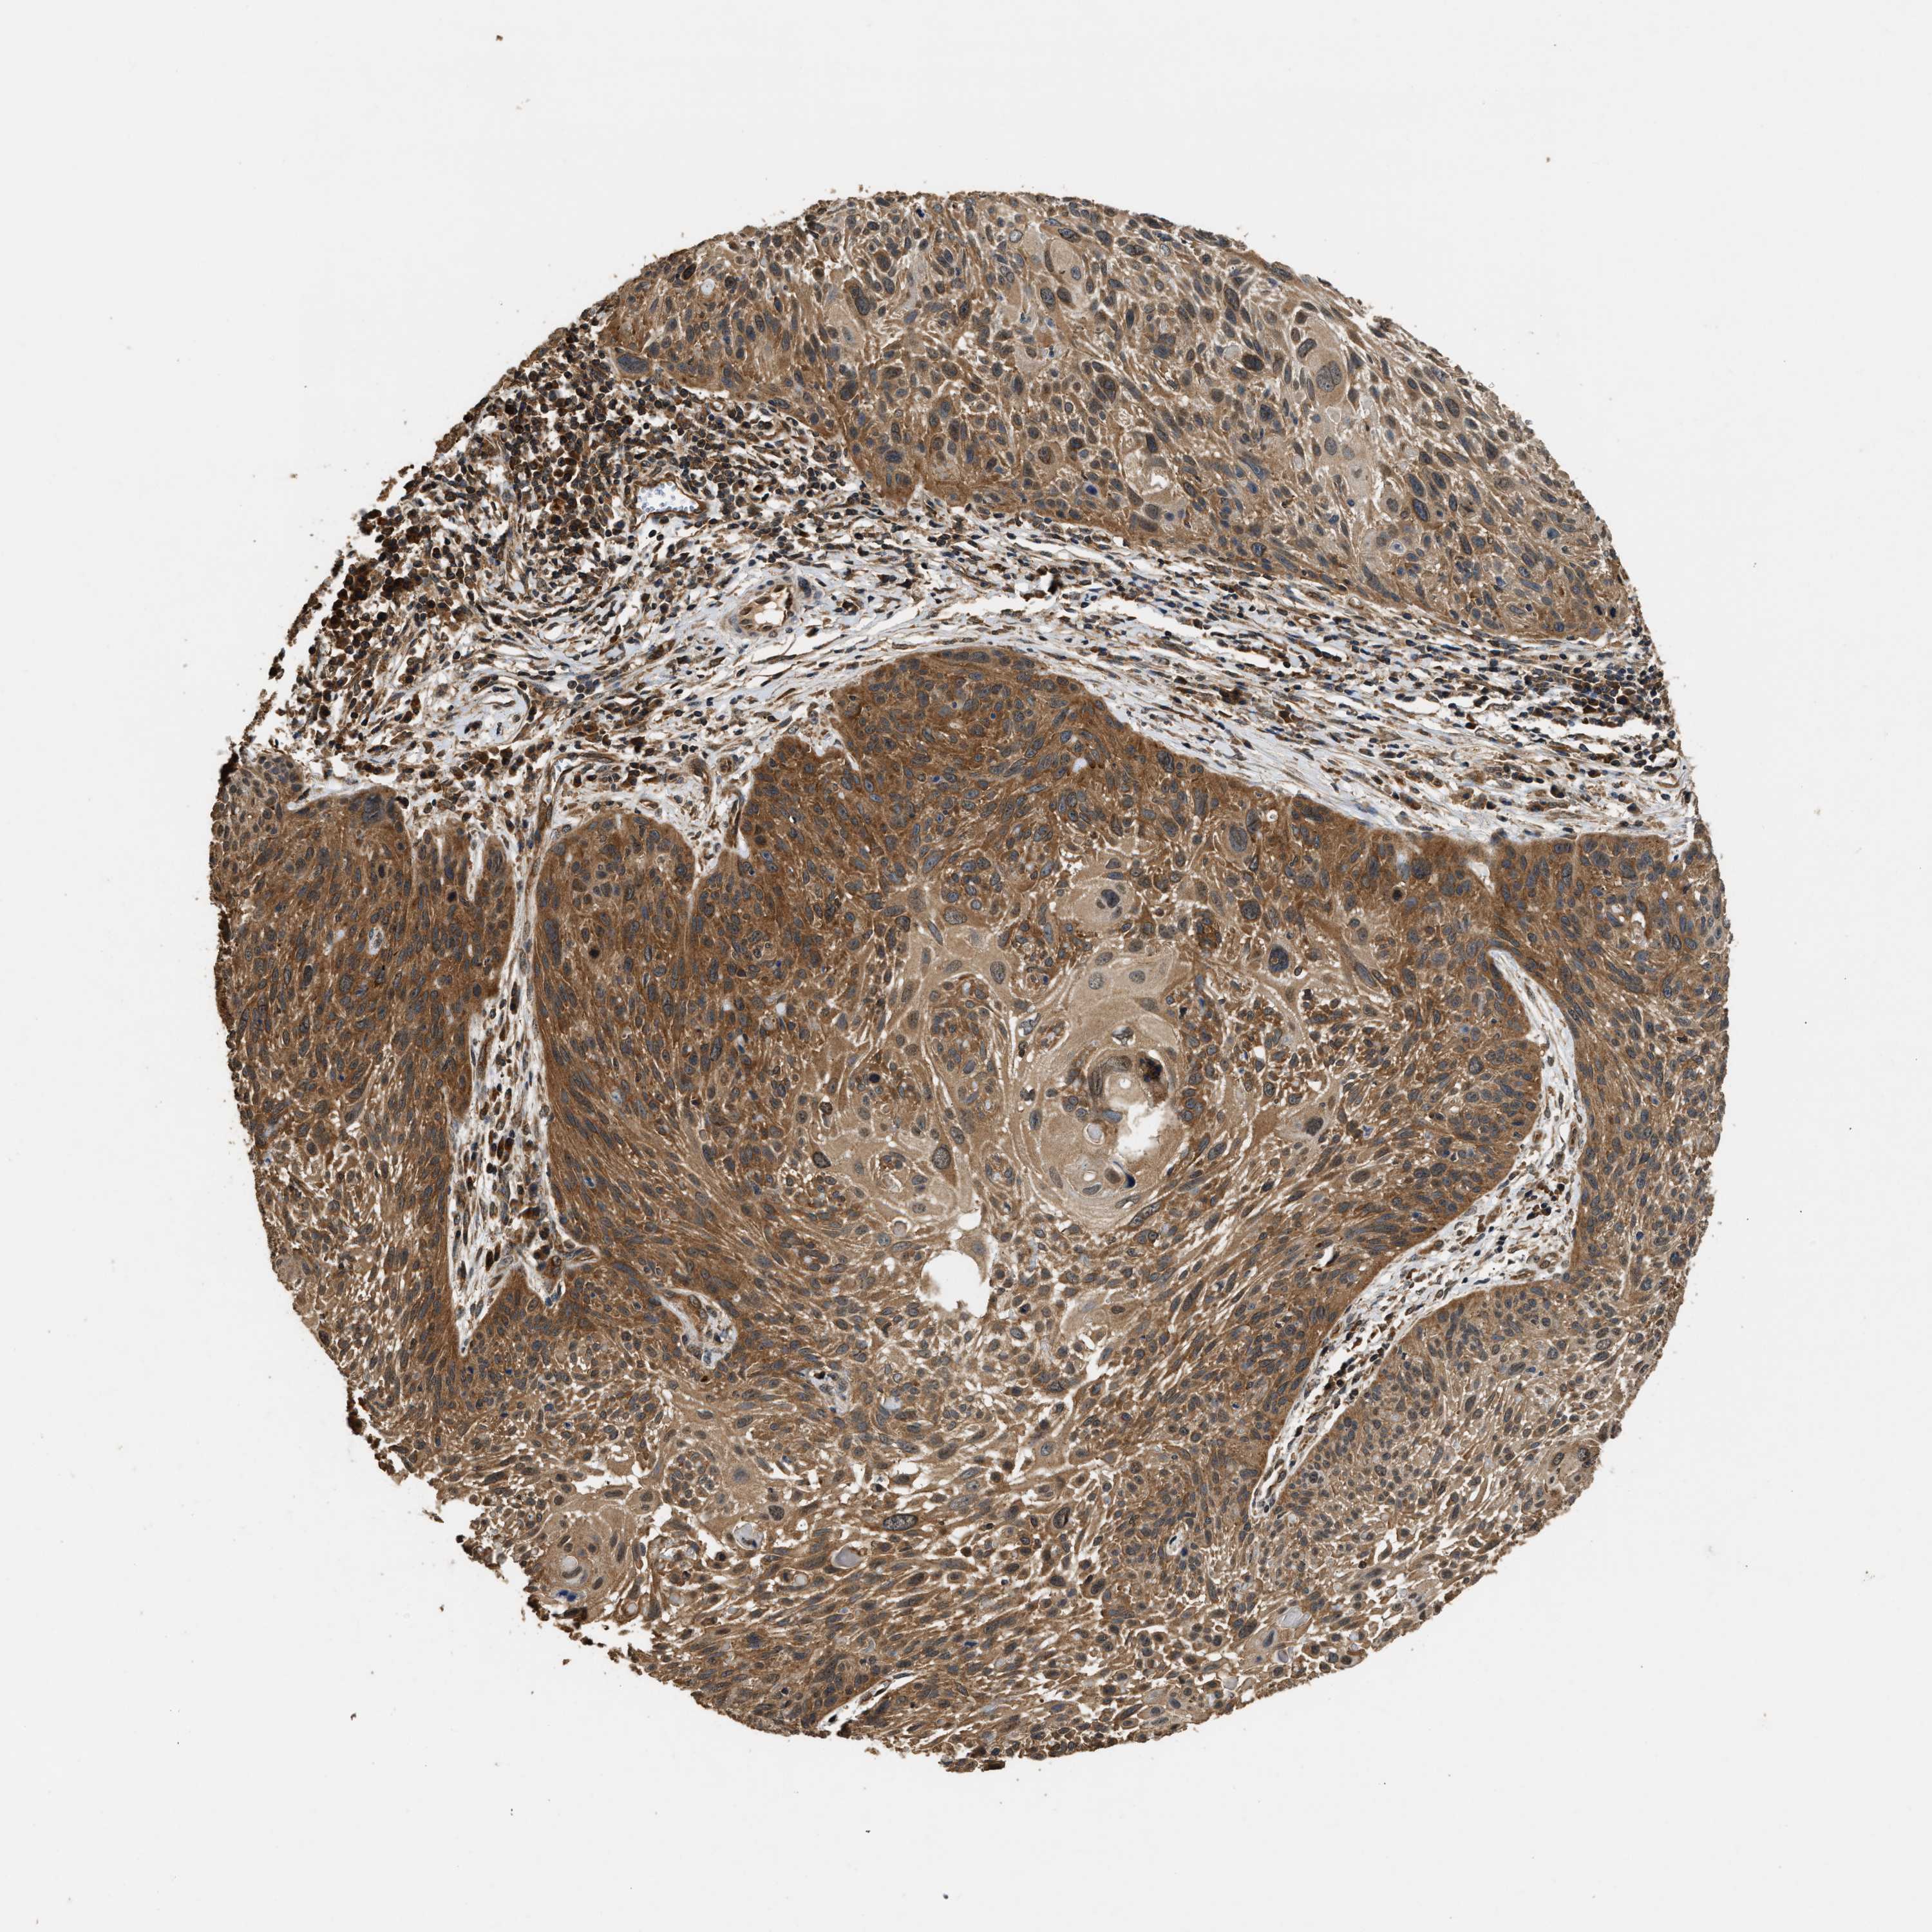

CERVICAL CANCER - Protein expressioni

A mouse-over function shows sample information and annotation data. Click on an image to view it in a full screen mode. Samples can be filtered based on level of antibody staining by selecting one or several of the following categories: high, medium, low and not detected. The assay and annotation is described here.

Note that samples used for immunohistochemistry by the Human Protein Atlas do not correspond to samples in the TCGA dataset.

Antibody stainingi

Antibody staining in the annotated cell types in the current human tissue is reported as not detected, low, medium, or high, based on conventional immunohistochemistry profiling in selected tissues. This score is based on the combination of the staining intensity and fraction of stained cells.

Each image is clickable and will lead to virtual microscopy that enables deeper exploration of all samples and also displays staining intensity scores, fraction scores and subcellular localization as well as patient and tissue information for each sample.

Antibody HPA020454

Staining

High

Medium

Low

Not detected

Intensity

Strong

Moderate

Weak

Negative

Quantity

>75%

75%-25%

<25%

None

Location

Nuclear

Cytoplasmic/membranous

Cytoplasmic/membranous,nuclear

Squamous cell carcinoma, NOS

Adenocarcinoma, NOS